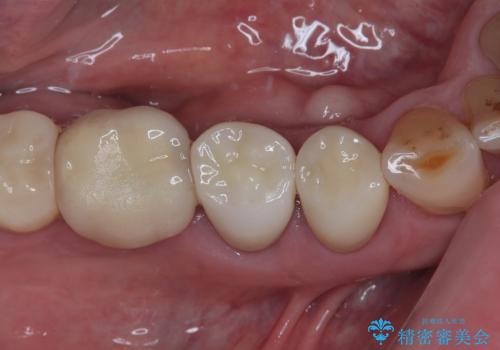

【セラミッククラウン】詰め物と歯の境目に汚れが溜まる

担当医 町田睦月

深い虫歯 セラミッククラウンの精度を高める歯周外科手術